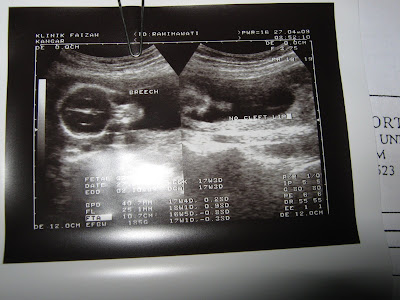

Terkejut dengan Gambar Kat atas nie, aku lagilah.....Ye kawan2 ku sekalian Alam...bahawasanya Penyakit Yang Berada kat Mama Mencah dah Berjangkit dengan Mama Qashrina "aku la tu"

period aku jalan seperti biasa..cuma pagi2 ja morning sickness , aku ingatkan biasa..ala alahan ubat perancang..lepas tu test Pregnant x mengandung pun, tapi oleh sebab sakit belakang ( ingatkan expect dari ubat bius) so aku ajak la hubby aku p Klinik Bersalin Doc Suraya( dalam Kangar nie dia ja doc Perempuan yang buka Klinik Time malam) . Apa lagi ..scan la ..."

Tahniah ..." Doc said..

ye..dah 4 bulan"..aku menyelit"

xkan doc, period saya normal".."ye nie gambar scan saya kasi" said Doc suraya..."Rezeki" kata nurse masa aku ambik ubat..ye memang Rezeki tapi dari segi mental"

Sayang akan dapat adik Oktober nanti. Jangkaan Doc 04 Oct 2009...

Sorry Gambar Terbalik , malas nak edit he..he..